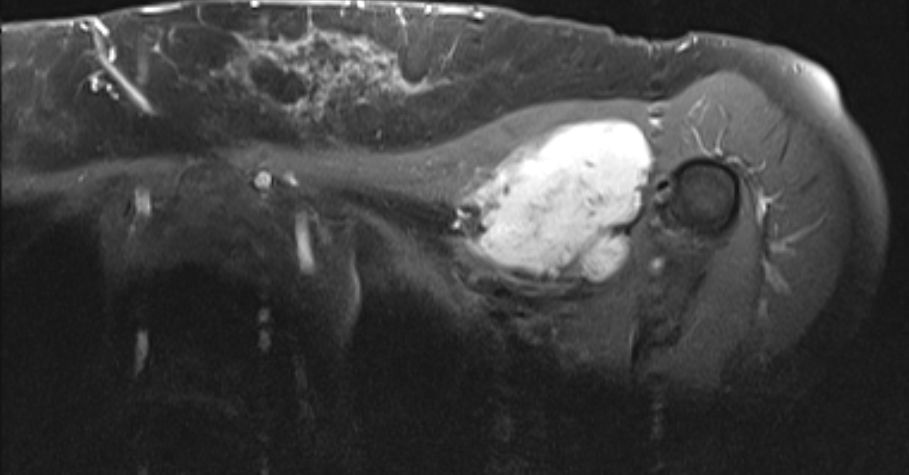

| Diagnostik | 56-jährige Frau mit einer derben, wenig verschieblichen Tumorbildung untergalb der linken Clavikula. ![]() |